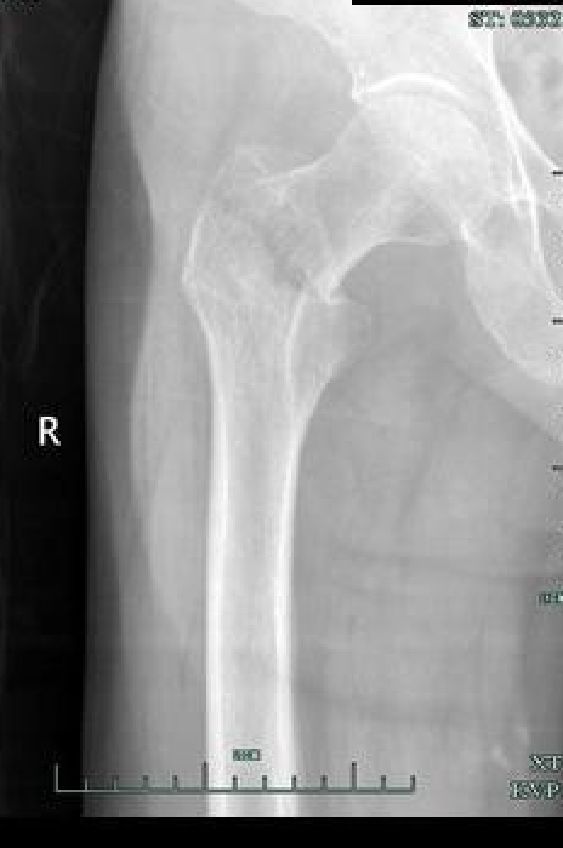

DHS(Dynamic Hip Screw)动力髋螺钉

以一根粗大宽螺纹的拉力螺钉与套管钢板及加压螺钉连接。在复位及骨折愈合过程中可使两骨折端靠拢,产生静力加压作用。对于顺转子间骨折线骨折可获得动力加压作用。

稳定骨折,固定成功

不稳定骨折,固定失败

用于骨质疏松患者有一定螺钉切除率,尤其是当拉力螺钉位置偏上时;

因钢板位于负重力线外侧,固定力臂较大,不适用于逆转子骨折。